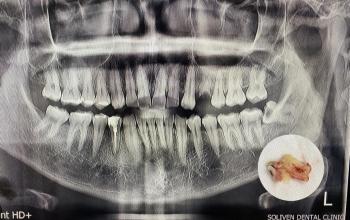

Image Observations: The photograph shows the lower front teeth (mandibular incisors) and the gum line.

Heavy Calculus/Tartar: There is a significant, thick band of yellow/brown, hard material covering the base of the teeth, especially noticeable between the teeth (interproximal areas) and along the gum line (lingual/tongue side). This is severe dental calculus (tartar).

Inflammation: The gums (gingiva) appear red, swollen, and possibly tender, which is consistent with gingivitis caused by the heavy calculus buildup.

Staining: The yellow color is due to a combination of extrinsic staining and the color of the calculus itself.

Diagnosis: Severe Gingivitis and Heavy Dental Calculus

The primary issue is the heavy buildup of calculus, which is actively irritating the gums and causing an inflammatory response known as gingivitis. If the condition is advanced, it may have already progressed to periodontitis, which involves irreversible bone loss around the teeth.